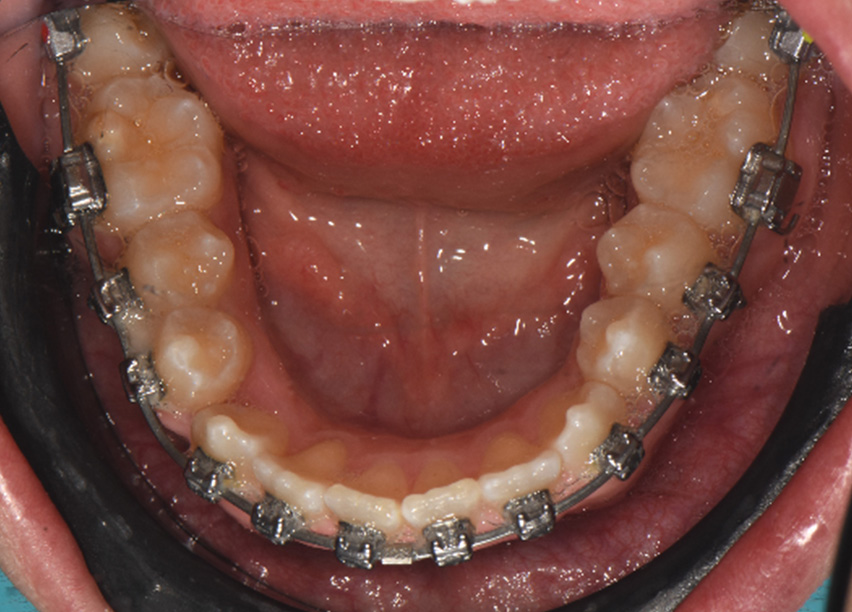

A 14-year-old male patient presented with a Class II sub-division 2 malocclusion with significant maxillary and mandibular crowding. The facial profile was convex with a slightly retrusive mandible, tendency to deep bite. Normal upper and lower first incisor inclination was measured, protruded upper and lower lip were noted. A constricted arch form with tapered buccal segments resulted in poor smile width and dark buccal corridors. Along with a reverse smile arc due to insufficient incisor eruption, this resulted in poor smile aesthetics.

The objectives were to create space while maintaining maxillary incisor position, improve the smile arc by erupting incisors, and develop the posterior segments for increased arch length, as well as improved smile width. Resolving crowding through arch development with proper torque control was a key objective, since incisor advancement and increased angulation would damage smile aesthetic and would result in a more pronounced lip. A non-extraction plan was chosen using Damon Ultima PSL System with Ultima wires, along with the use of anterior bite turbos and light elastics for early deep bite and Class II correction.

Variable torque Damon Ultima brackets were chosen for this case. Neutral torque on U2-2 & L1 & L3, proclined torque on U3, retroclined torque on L2 due to crowding and objective of torque control. All permanent teeth were bonded, the bite was disarticulated. The U2-2 brackets were positioned vertically higher to improve the smile arc.

Observations: At the end of phase 1, most of the rotations had been corrected and arch development was progressing well. The crowding had been resolved and spaces were visible due to arch development with the first rectangular wire. Additionally, primary torque control was observed. The time frame of these changes was six months.

Observations: Arch form was really improved in both shape and width. The variable torques allowed the Ultima wires to express the deflection and the torque changes were very close to the final goals. The time frame was 3 months.